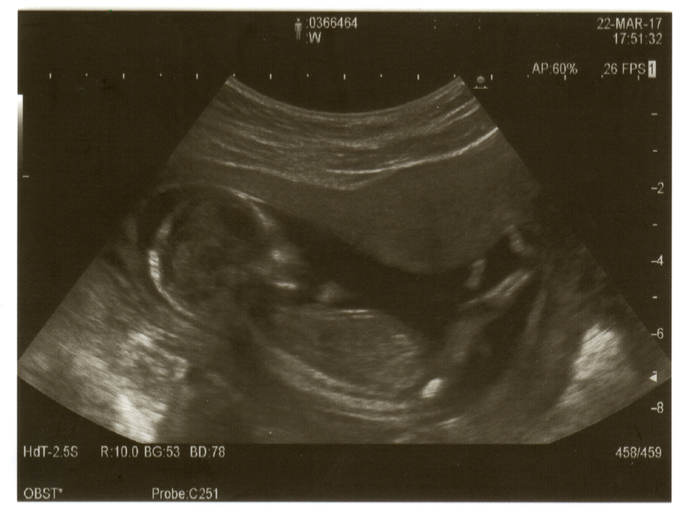

A new study has shown that the placenta also plays a role in fetal penis development by producing a second hormone outside the testes.

Fetal external genitalia are initially identical and go through male and female differentiation that is determined by chromosomal, genetic and hormonal factors. During the early stages of male fetus development, a gene on the Y chromosome tells the fetal tissue that will form the sex organs to become the testes. These secrete testosterone, a steroid hormone that is subsequently converted into dihydrotestosterone (DHT) by enzymes in the genital tubercle – the primordial structure that either develops into a penis or clitoris, depending on its exposure to hormones released by the developing gonads (ovaries or testicle). The conversion of testosterone to DHT within the tissue is crucial for penis development. Partially supported by the EU-funded REEF project, a team of researchers have shown that in addition to this canonical androgenic pathway, the masculinisation process also involves an alternative (backdoor) pathway through the production of androsterone, which originates in other tissues, including the placenta. The findings were published in the journal ‘PLOS Biology’(opens in new window). “Recently, an alternative “backdoor” route to the formation of DHT, which does not require testosterone, has also been shown to be essential for normal development of the human penis. In this study we provide evidence indicating that androsterone is the major backdoor androgen involved in human masculinization and that it is produced in nongonadal tissues.” The research concluded “that masculinization of the human fetus depends on steroid hormone secretion from both the testes and the placenta, and would explain why placental dysfunction is associated with disorders of sex development.” A press release(opens in new window) explains the study’s methodology: “To learn more about this pathway, the authors used mass-spectrometry to measure levels of different steroids in fetal plasma and tissue during the second trimester, when the most critical steps in penis development occur.” Birth defects As noted in the British edition of ‘The Conversation’(opens in new window), it’s crucial to analyse the pathways that control the male external genitalia. “Disorders affecting penis development are among the most common birth defects seen in humans,” it says. “The most frequent of these abnormalities is hypospadias, which is characterized by abnormal opening of the urethra on the ventral side of the penis,” according to ‘PLOS Biology’. An article in the ‘European Journal of Pediatrics’(opens in new window) notes that this condition’s prevalence in Europe “is approximately 18.6 per 10,000 births.” Despite varying temporal trends, “hypospadias registered between 2001 and 2010 in 23 EUROCAT registries revealed a stable number,” the same article adds. Highlighting the causes of this condition, the article refers to various factors “including genetic predisposition, inadequate hormonal stimulation prenatally, maternal-placental factors, and environmental influences.” Indeed, in recent years, several studies have analysed the impact of environmental factors, such as endocrine disrupting compounds (EDCs) on reproductive development. EDCs are man-made chemicals used in many industries, including the production of plastics, cosmetics and pesticides. The REEF (Reproductive effects of environmental chemicals in females) project that provided partial funding to the research also focused on this issue. It examined how environmental chemicals affected the female reproductive system and found that “there was a unifying conclusion regarding the damaging effects of certain chemicals,” as stated on CORDIS(opens in new window). For more information, please see: CORDIS project web page(opens in new window)